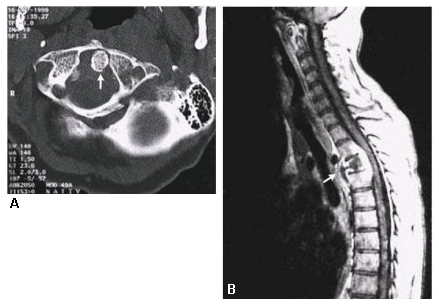

Skeletal TB: results from haematogenous spread. The most common sites of involvement are the vertebral column (especially the lower thoracic and lumbar regions), hip, and knee. TB involving the spine is also known as Pott's disease. TB in the joints is usually monoarticular. [Figure caption and citation for the preceding image starts]: CT showing spinal TB (Pott's disease)Massachusetts Medical Society; reproduced with permission from N Engl J Med. 2002;347:1849; used with permission [Citation ends].